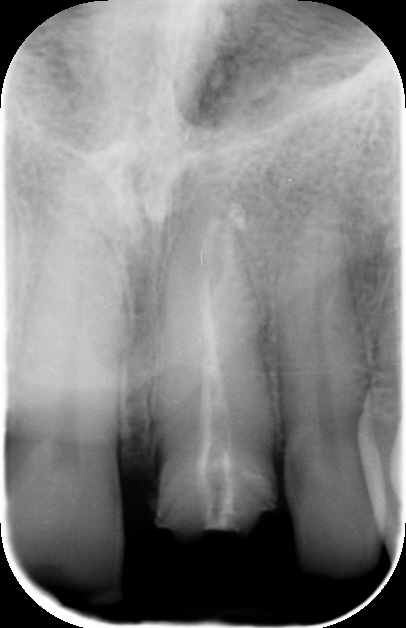

Trattamento endodontico inadeguato: il precedente trattamento canalare era insufficiente, lasciando il dente vulnerabile a infezioni e compromettendone la prognosi a lungo termine.

Trattamento Canalare Incongruo

1. Ritrattamento Endodontico

Il primo step è stato il ritrattamento endodontico, essenziale per garantire la salute a lungo termine del dente. Dopo la rimozione della vecchia otturazione canalare, è stata effettuata una detersione accurata con irriganti specifici e successiva otturazione tridimensionale per prevenire recidive infettive.

Radiotrasparenza, permettendo un migliore controllo radiografico nel tempo.